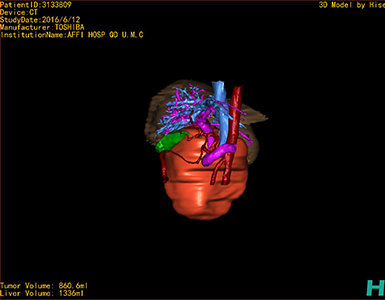

通过调节窗宽窗位调整CT序号,对肿瘤,肝实质,胆囊,下腔静脉,肿瘤,肝动脉、门静脉及肝静脉等进行三维重建;系统自动计算肿瘤体积和肝脏体积。

模拟手术操作,自动计算切除肿瘤体积。肝脏体积为1336ml,肿瘤体积为860.6ml,肿瘤体积为肝脏体积的64.4%,通过比对30-40岁正常肝脏体积为1323.35±298.47 ml,通过术前模拟手术,精准判断切除后剩余肝脏体积能耐受,避免肝衰竭发生。

术前三维重建:重建图片